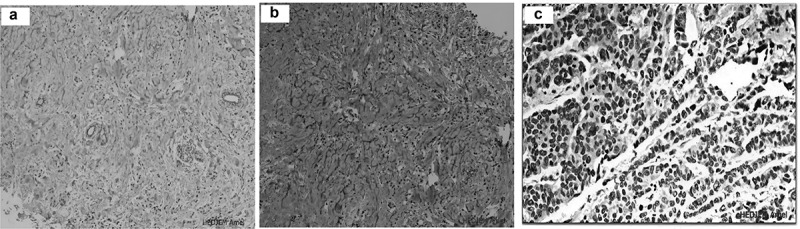

三阴性乳腺癌(TNBC)是一种以缺乏雌激素和孕激素受体以及缺乏HER2过表达为特征的乳腺癌分子亚型。TNBC是高度异质性的,使新的治疗靶点的确定复杂化。然而,雄激素受体(AR)在腔内雄激素受体(LAR TNBC)亚群中的表达为替代治疗方法打开了大门。本研究旨在评估2015年2月至2017年2月接受治疗的160例早期TNBC患者的AR表达及其与临床病理因素的相关性。我们的研究结果显示,在≥1%的AR阳性病例中,有16.87%(27/160)的患者存在AR表达。此外,在≥10%的AR阳性病例中发现12.5%(20/160)。AR阳性表达与高Ki-67增殖指数和基础免疫表型呈负相关。我们队列的5年生存率为83.12%,AR表达与总生存率无显著相关性(p = 0.77)。该研究强调了AR表达在TNBC中的潜在作用及其对治疗策略的影响,尽管没有发现与总生存率的显著关联。

Triple-negative breast cancer (TNBC) is a molecular subtype of breast cancer characterized by the absence of estrogen and progesterone receptors and the lack of HER2 overexpression. TNBC is highly heterogeneous, complicating the identification of new therapeutic targets. However, the expression of the androgen receptor (AR) in the luminal androgen receptor (LAR TNBC) subgroup has opened the door to alternative therapeutic approaches. This study aimed to assess AR expression and correlate it with clinicopathological factors in 160 early-stage TNBC patients treated from February 2015 to February 2017. Our findings reveal that AR expression is observed in 16.87% (27/160) of ≥1% AR positivity cases. Moreover, a significant 12.5% (20/160) was found in ≥10% AR positive cases. Positive AR expression was inversely correlated with a high Ki-67 proliferation index and with the basal immunophenotype. The five-year survival rate for our cohort was 83.12%, and no significant association between AR expression and overall survival was observed (p = 0.77). The study highlights the potential role of AR expression in TNBC and its implications for therapeutic strategies, although no significant association with overall survival was found.